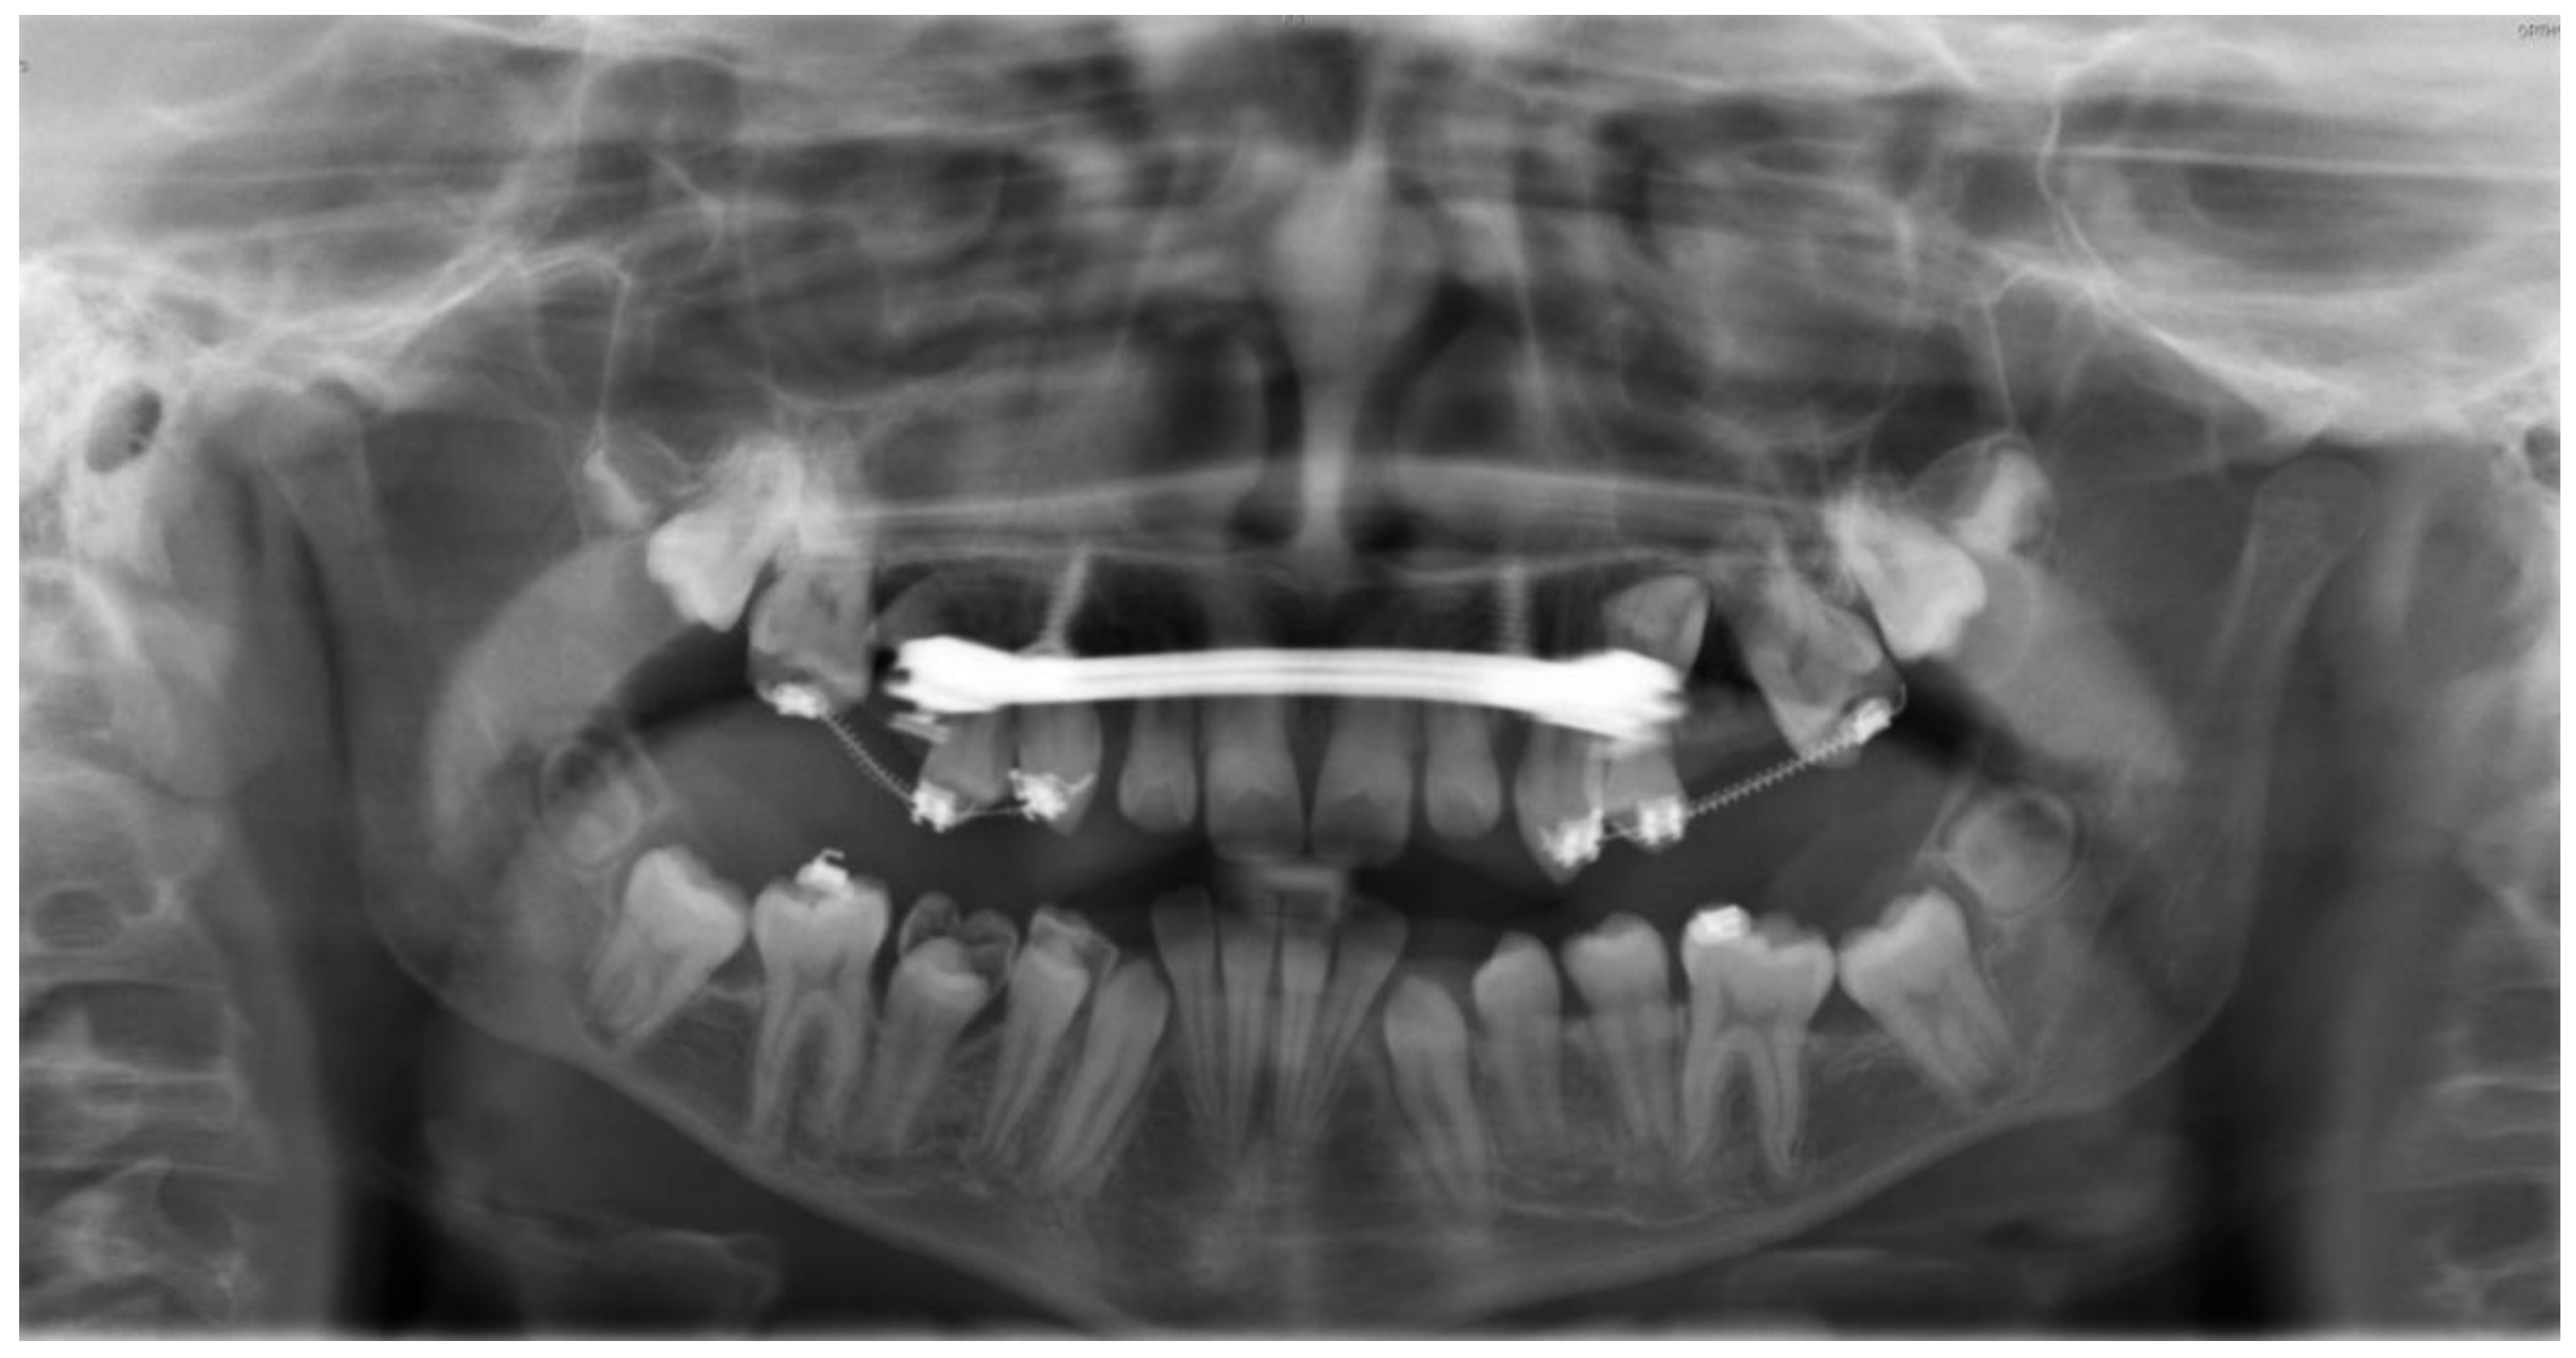

2.4.1. First Surgical Exposure of the Impacted Teeth and Insertion of the Mini-Implants

2.4.2. RPE Using the Skeletal-Anchorage Hyrax Appliance

2.4.3. Alignment of the Surgically Exposed Teeth by Using Skeletal Anchorage